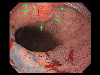

A case of IIc+IIa type early gastric cancer which invaded the esophagus.

Endoscopy